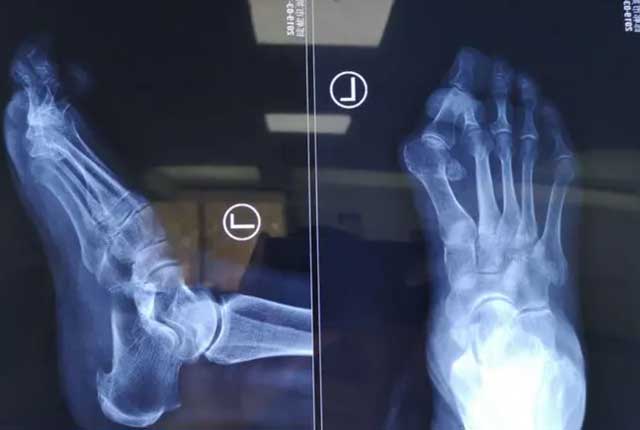

拇外翻是最為常見的足部畸形之一,是指拇趾在第一跖趾關節處向外側偏斜移位。該病多發于中老年女性、及長期穿高跟鞋、尖頭鞋的女性,同時具有家族遺傳傾向。隨著疾病的發展可出現拇指及相鄰腳趾的畸形、拇囊炎、腫痛、關節炎等,嚴重者可活動受限,行走疼痛困難,給患者帶來諸多身心健康危害。本期永林中西醫結合醫院骨傷科矯形專家趙憲光主任為大家講解拇外翻相關防治問題。